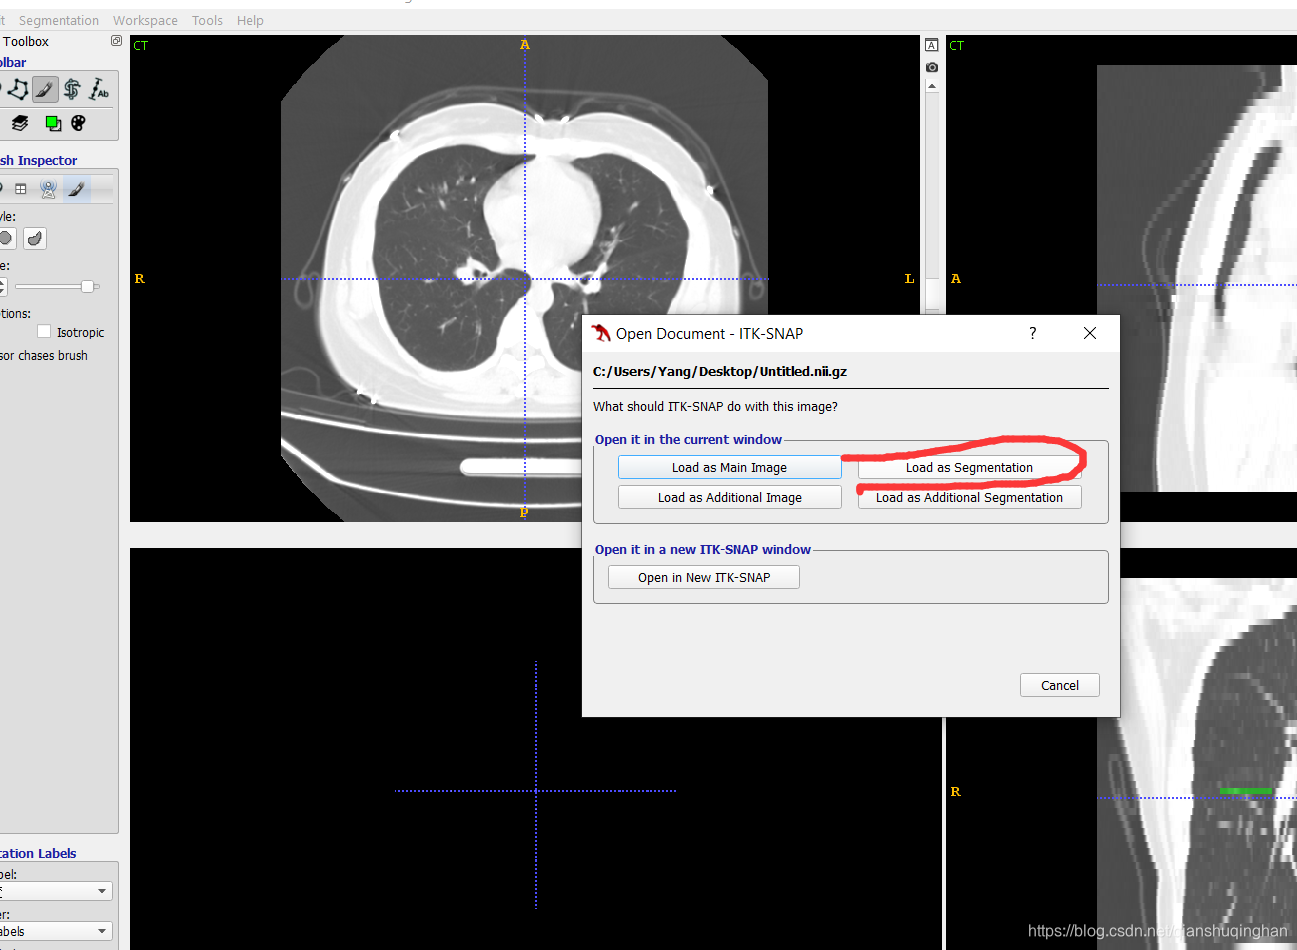

载入此前标注的mask文件

从菜单栏Segmentation->Upload Segmentation 选择mask文件载入;

或者直接拖拽进软件窗口。

然后选择Load As Segmentation即可。